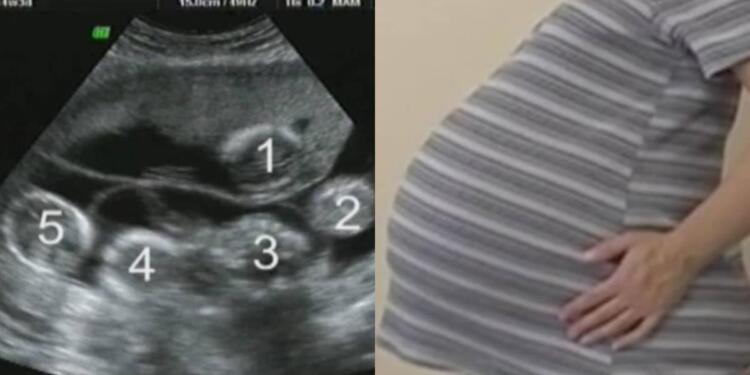

Η ιστορία θα μπορούσε να είχε τελειώσει εδώ, αλλά δεν ήταν γραφτό. Την επόμενη φορά που πήγαν στον γιατρό, υπήρχαν ακόμα δύο παλμοί. Ένας, δύο – δίδυμα. Όμως, υπήρχε και τρίτος… και τέταρτος. Και δεν σταματούσε εκεί. Υπήρχαν 5 παλμοί, 5 μωρά στην κοιλιά της. Η Rachelle ήταν έγκυος σε πεντάδυμα, κάτι συμβαίνει μερικές φορές σε άτομα που κάνουν θεραπείες γονιμότητας.

Ήρθαν αντιμέτωποι με μια πολύ δύσκολη απόφαση, αλλά στο τέλος ο Jayson και η Rachelle αποφάσισαν να συνεχίσουν την επικίνδυνη εγκυμοσύνη, ελπίζοντας ότι τα μωρά θα τα κατάφερναν. Κόντρα σε όλες τις πιθανότητες, τα μωρά αναπτύχθηκαν μια χαρά! Πόσο τυχεροί ήταν που η ιστορία πήρε αυτή την τροπή. Η κοιλιά της Rachelle μεγάλωνε όλο και περισσότερο. Εδώ είναι στις 33 εβδομάδες: